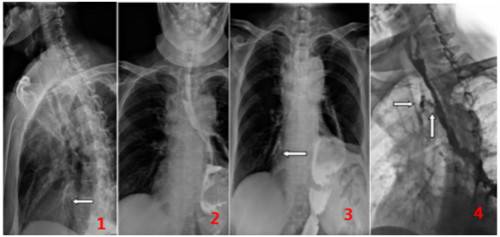

2016年7月,秦某某,女,60岁,食道癌术后半年,近十余天进食后呛咳,到医院就诊,做食道碘水造影检查。检查过程中采用数字透视观察造影剂流动情况,并对特征影像进行实时高清点片,获取图像如下:

图1.3:左箭头示碘水进入右肺下叶支气管。图4:右箭头示植入支架的气管管腔内见碘水影。下箭头示造影剂经食管前壁不规则形、窄小瘘口进入气管内。通过上述症状,可以判断该患者存在食管气管瘘。综上所述,可以判定食管气管瘘具体病变。